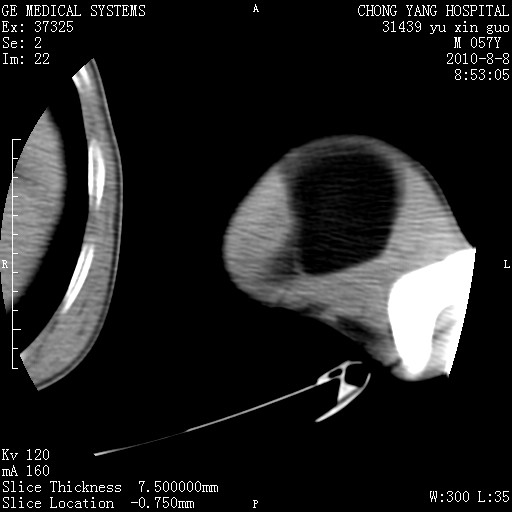

标题: CT28267:M57Y 上臂包块8年余。 [打印本页]

标题: CT28267:M57Y 上臂包块8年余。

包膜光滑、完整的脂肪密度肿块,支持脂肪瘤。